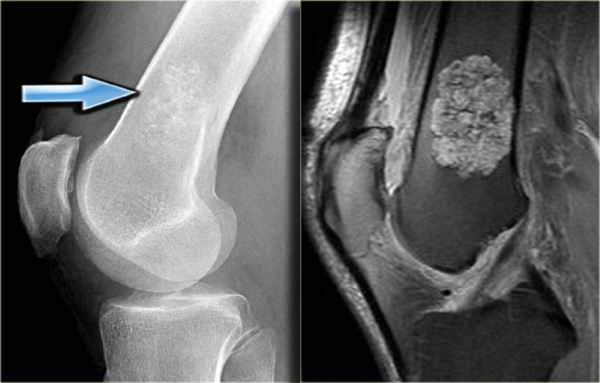

Врачи отмечают, что энхондрома, доброкачественная опухоль хрящевой ткани, часто проявляется бессимптомно, что затрудняет ее раннюю диагностику. Однако в некоторых случаях пациенты могут испытывать боль в области пораженной кости, особенно при физической нагрузке. Также возможны отеки и деформация конечностей. При подозрении на энхондрому важно провести рентгенографию или МРТ для точного определения локализации и размера опухоли.

Постановка диагноза и его подтверждение происходит поэтапно. Сначала собирается анамнез, выявляются предрасполагающие факторы и патологии, способствующие развитию заболевания. Затем проводится осмотр пациента и пальпация выступающего участка кости. Для подтверждения диагноза и определения типа опухоли используется аппаратная диагностика:

- МРТ и КТ — позволяют увидеть наличие опухоли, её структуру и тип. Злокачественные формы хорошо визуализируются на рентген-контрасте.

- Рентгенография — помогает определить наличие опухоли и её локализацию, но не предоставляет точной информации о структуре и типе новообразования.

Как выглядит энхондрома?

Энхондрома на рентгеновских снимках обычно выглядит как овальное или округлое просветление (участок пониженной плотности) внутри кости с тонкой кортикальной оболочкой и возможными внутренними кальцификациями.